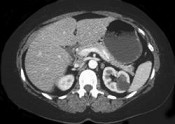

- 单项选择题女性,最近感腰部胀痛, 体检发现B超右肾正常,左肾有一囊肿, 双肾体积不增大,尿常规、肾功能正常, 无家族病史,CT表现如图所示, 最可能考虑为 ( )